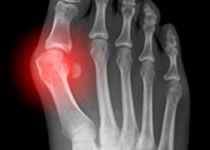

Artritis reumatoide